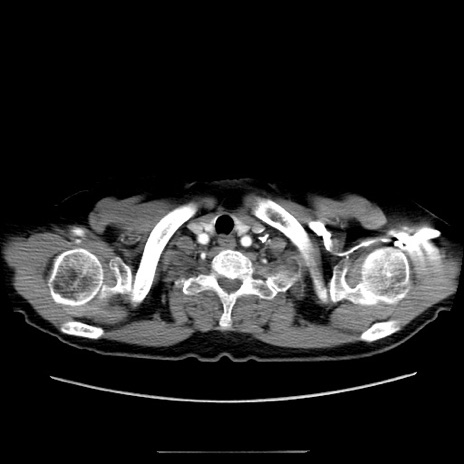

症例5(横断像)

【症例】70歳代女性

【主訴】お腹が張る

【現病歴】1週間くらい前から腹部膨満の自覚あり。昨日夜から増悪したため、本日救急外来受診。

【身体所見】意識清明、BT 36.5℃、BP 165/106mmHg、HR 80bpm、SpO2 98%、腹部:膨満、軟、自発痛・圧痛なし、触診にて不快感あり、腸蠕動音:減弱

【データ】WBC 12600、CRP 1.04